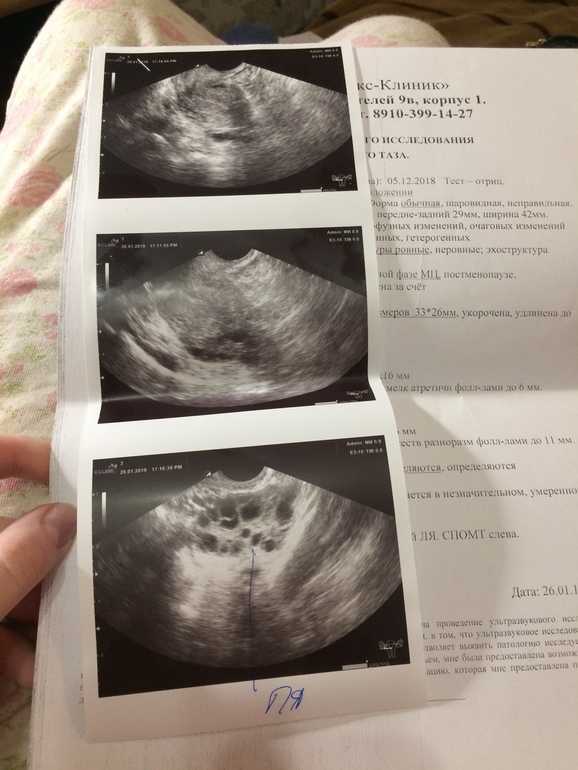

Сделала УЗИ... Надеялась на беременность.... Предстоит лечение... Очень хочется малыша... Я, надеюсь, что у нас ещё все получится и мы станем родителями... Ну, почему так, кто не хочет детей, то у них получается, а мы хотим.... и никак.... Я понимаю, что это не приговор, что все лечится, что я ещё юная и все впереди... Одно радует, что это все выявила на ранних стадиях и все можно вылечить...

В понедельник пойду записываться ко врачу, уже думаю она мне все подробнее расскажет... На фото есть снимок матки, я все думаю может там что-то есть и она просто не заметила...?

Если Вы имеете в виду плолное яйцо? То его там нет

У меня последние дни были 5.12, сегодня на УЗИ сказали, что даже не собираются

Так что я даже не знаю.... Без лечения, думаю, ничего не светит...